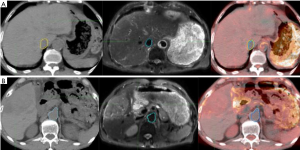

One patient is described as an example. Automatic deformation registration was used. When automatic deformation registration was used, the maximal observed displacements of the bifurcation point in the portal vein was 2.5, 1.0 and 2.0 mm along X-axes, Y-axes and Z-axes. The maximal observed displacements of the celiac trunk were 3.0, 1.8 and 1.0 mm along X-axes, Y-axes, Z-axes. After using the Reg Refine registration tool, the maximal observed displacements of the bifurcation point in the portal vein was 0.5, 0.5 and 1.0 mm along the X-axes, Y-axes and Z-axes. The maximal observed displacements of the celiac trunk were 0.5, 0.6 and 1.0 mm along X-axes, Y-axes, Z-axes (Figure 1).

Comparison of GTVs before and after DR

GTVs obtained from 4DCT images were increased by an average of 4.23% (P<0.05) after DR, with GTVs following DR of each phase consistent with T2-weighted MRI image basic volume (Table 3, Figures 2,3). After DR all 4DCT image phases GTV were larger than DR before (except CT90, P<0.05).